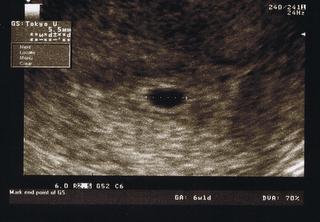

Melduje się po wizycie, Na USG widoczny pęcherzyk 6 mm z ciałkiem żółtym, ładny okrąglutki, lekarz mówi, że wszystko na dobrej drodze, za tydzień mam przyjść na kontrolne USG, co mnie zaskoczyło Bezpłatne - żeby zobaczyć zarodek i ewentualnie serduszko mówiłam mu że cykle z reguły mam 31-32 dni więc podejrzewam owulację późno:) Cieszy mnie to, że ciąża umiejscowiła się prawidłowo w macicy, karte ciaży mi już też założył, przepisał mi także luteine dopochwowo na te bóle podbrzusza, dał też nr komórki w razie gdybym nie daj Boże zaczeła plamić itp. Tak więc z wizyty jestem zadowolona :) aaaa i według USG to 5 tydzień TP wyznaczył na 08.04.2014r.

Zobacz załącznik 576232

Idąc za Twoim przykładem i próbując się nie zamartwiać ja też wklejam swój pęcherzyk..a co tam. Liczę, że jednak zobaczę coś tam więcej za te dwa tygodnie....

usg.jpg

Ja na USG byłam w poniedziałek. Pęcherzyk ma 7,7 mm, ciałko żółte 2,3 mm. Na kolejne USG idę za ok. 3 tygodnie, czyli będę dokładnie w 8 tygodniu i 2 dniu. Wczoraj byłam u gina. Założył mi kartę przebiegu ciąży i zlecił badania, które mam zamiar zrobić za dwa tygodnie przed kolejną wizytą u niego. Także obecnie "cieszę się" piękną pogodą - przysypiając na biurku w pracy... nie mogę się powstrzymać :/.

To ja też się podzielę moją fasolką :)))

Pierwsze USG miałam 6 sierpnia :) a następna wizyta 4 września i już nie mogę się doczekać :))))